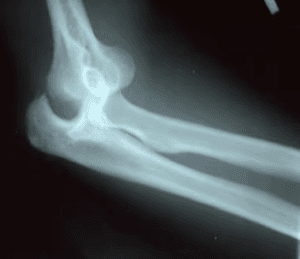

An X-ray is essential to identify any bone injuries and determine the direction of the dislocation.

X-rays are the preferred method for confirming elbow dislocation.

A computed tomography (CT) scan may be ordered if bone details are unclear on X-rays. While a magnetic resonance imaging (MRI) scan can help assess ligaments, it is typically unnecessary immediately following the dislocation. The physician will proceed with elbow reduction once the dislocation is confirmed by X-ray. Any subsequent CT or MRI scans are usually performed after the elbow has been repositioned.